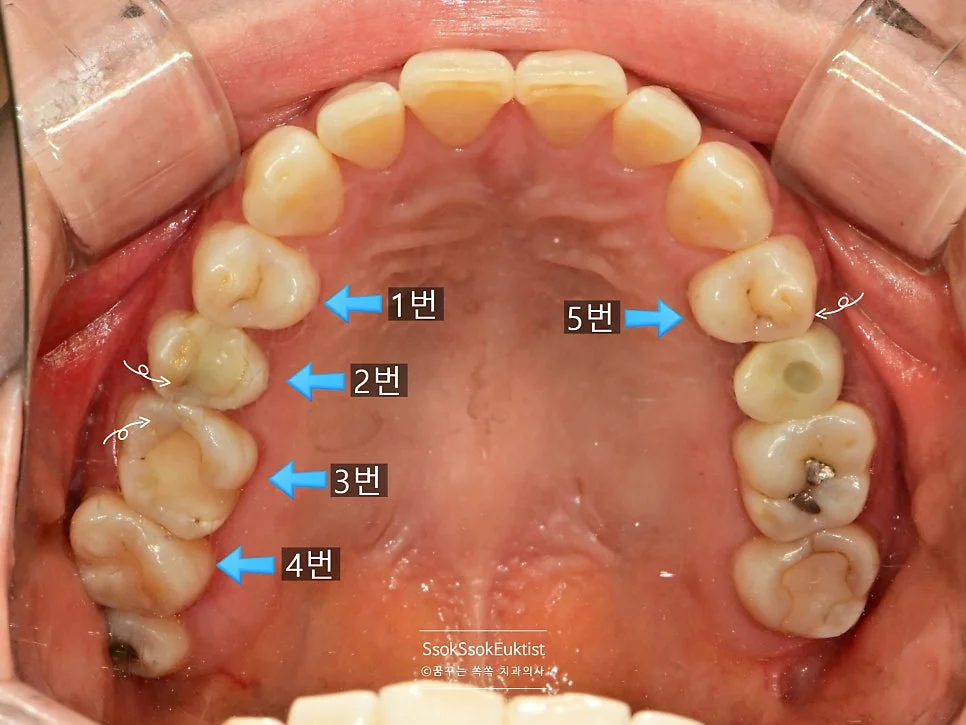

구강 사진에서 하얀색 화살표는 충치의 위치를, 파란색 화살표로는 해당 치아를 번호로 기재하였는데요. 각 치아의 치료 계획에 대해 말씀드리겠습니다.

- 2번 치아 → 충치가 있는 면과 기존 수복물을 모두 포함하는 치료 → 크라운 치료

- 1번 치아 → 2번 치아의 크라운 치료 시 인접한 면을 육안으로 확인 후, 치료가 필요한 만큼 충치가 있다면 레진으로 간단히 치료 (충치가 없으면 치료 X)

- 3번 치아 → 충치가 있는 면과 기존 수복물을 모두 포함하는 치료 → 크라운 치료

- 4번 치아 → 3번 치아의 크라운 치료 시 인접한 면을 육안으로 확인 후, 충치가 있다면 레진으로 간단히 치료

- 5번 치아 → 충치가 있는 면이 인접한 치아에 의해 막혀 있으므로 → 인레이 치료

- 6번 치아 → 충치가 있는 면이 인접한 치아에 의해 막혀 있으므로 → 인레이 치료

조금 어려울 수 있습니다만 천천히 설명드리겠습니다!

총 크라운 2개, 인레이 2개, 레진 가능성 치아 2개, 사랑니 발치 1개입니다.